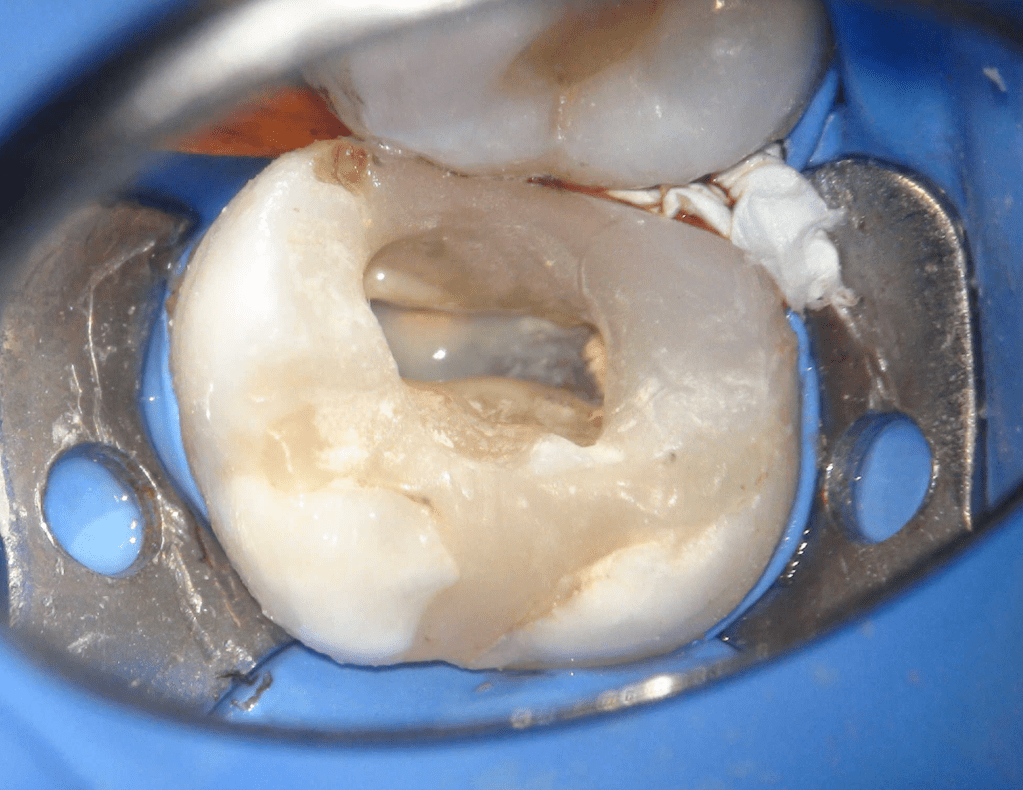

Reco pared vesticular